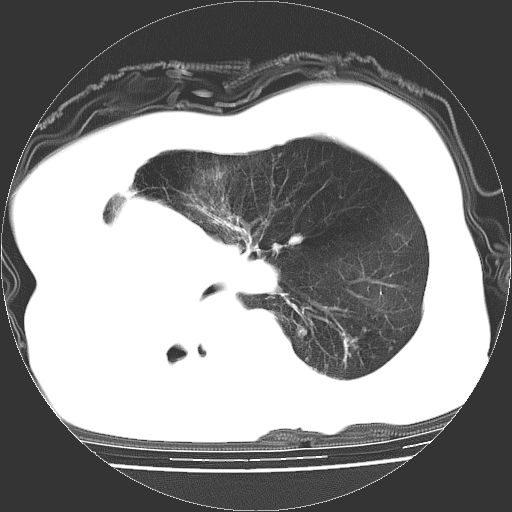

标题: CT23991:女,72岁,咳嗽、憋气一周。 [打印本页]

女,72岁,咳嗽、憋气一周,十年前曾患肺结核及胸膜结核。

右侧毁损肺,右侧纵隔疝

右侧毁损肺,右侧纵隔疝,左肺代偿!

右侧肺硬变,左肺代偿气肿。

1.右侧损毁肺伴胸膜钙化,2.左肺小结节灶,良性可能大,注意复查。3.肝脏左叶囊肿。4.先天性一侧肺不发育待出外(右侧胸廓无明显塌陷)。对比原片应该非常有帮助。

右侧肺毁损,左肺代偿性肺气肿,纵隔疝。